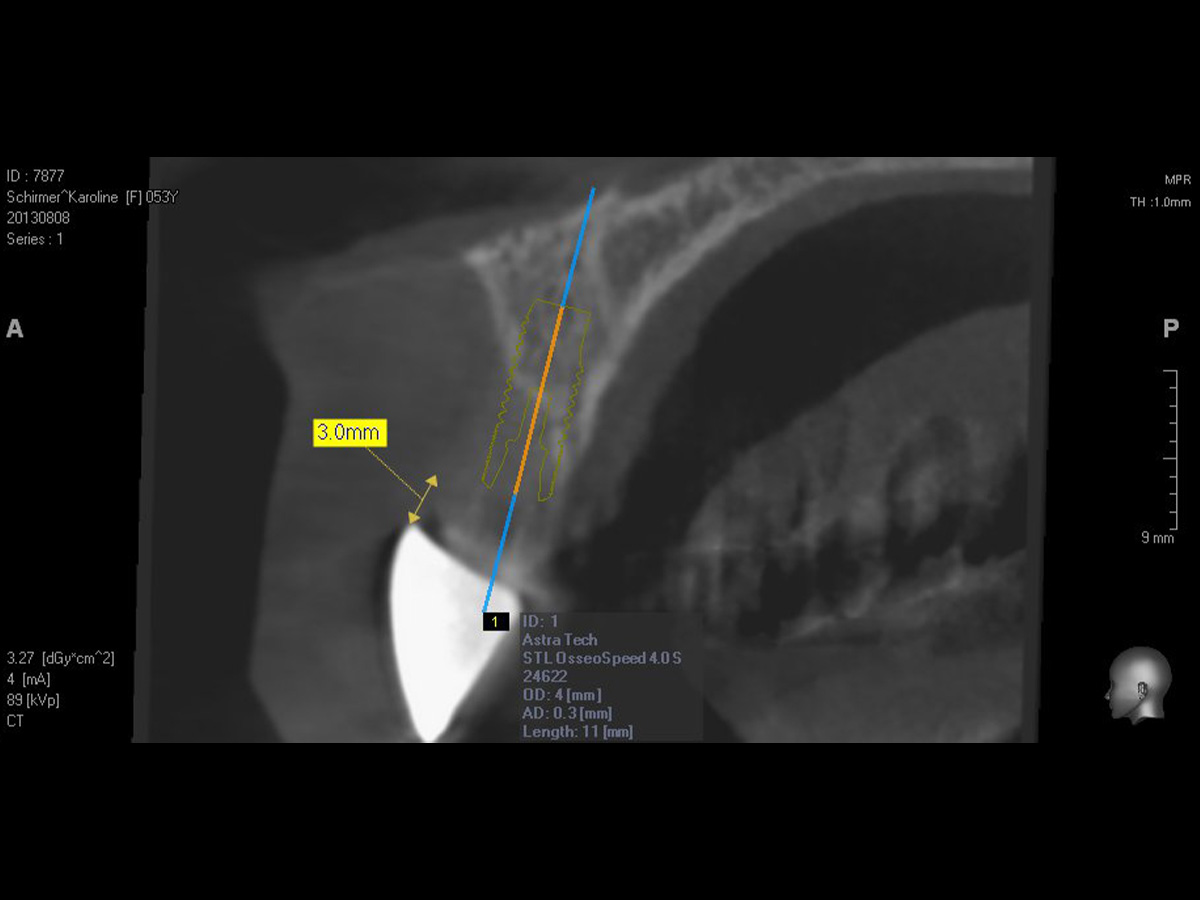

Abbildung 12

Implantation: Gutes Knochenvolumen in horizontaler und vertikaler Dimension.

Abbildung 13

Implantation in optimaler prothetischer Ausrichtung möglich, da ausreichendes knöchernes Angebot in vertikaler und horizontaler Dimension.